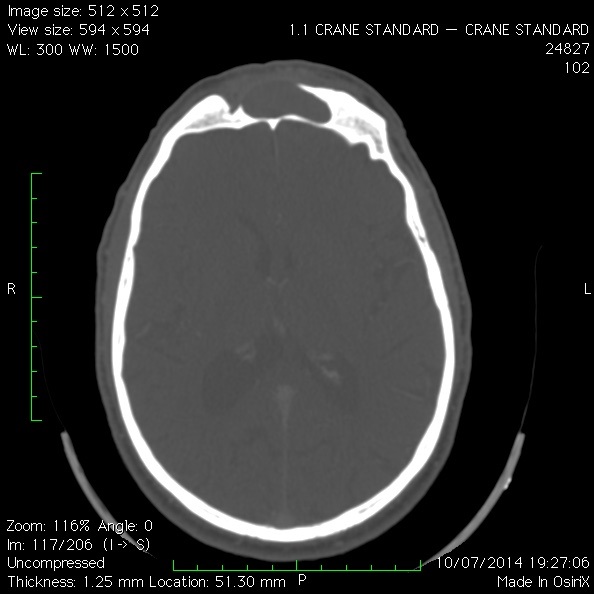

Le scanner des sinus

Cet examen d’imagerie est capital pour diagnostiquer la pathologie frontale (sinusite, mucocèle, papillome inversé, tumeur, brèches méningées, méningocèles), et pour planifier l’intervention. Il permet notamment au chirurgien d’utiliser une navigation assistée par ordinateur pour lui permettre de mieux se repérer dans les sinus (sorte de GPS chirurgical) dont la variabilité de l’anatomie est très importante.

Dans le Service ORL du CHU de Caen nous utilisons la neuronavigation magnétique Fiagon qui permet de naviguer à la fois avec un scanner mais aussi si besoin, avec une IRM.